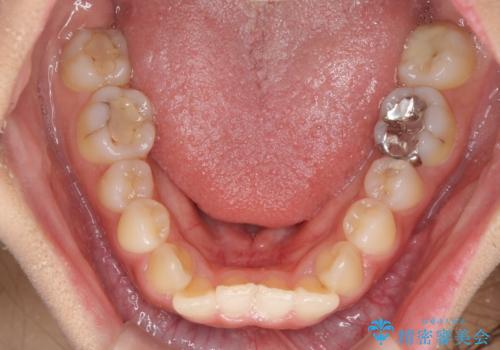

前歯の突出感とデコボコ インビザラインで改善

- 上下前歯のデコボコを気にして来院された患者様です。

インビザラインによる上下歯列の側方拡大と後方移動、IPR(歯と歯の間を削る)にるスペースの獲得により歯列を整えることとしました。

右上の小臼歯は歯根癒着をしており、様々な方法を試みるも動かすことができませんでした。

それでも奥歯のかみ合わせに不自由はなく、歯列をきれいに整えることができました。